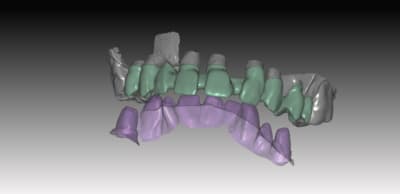

exemple de réalisation ..

sur ce cas pas de base titan, pas nécessaire because branemark , exagone externe base large ,bonne surface d'assise

Je posterais d autre cas sur du nobel activ (avec ambase ) strauman BL et NBreplace

faites l'économie d'un pilier , et appréciez le confort du transvissé :):)